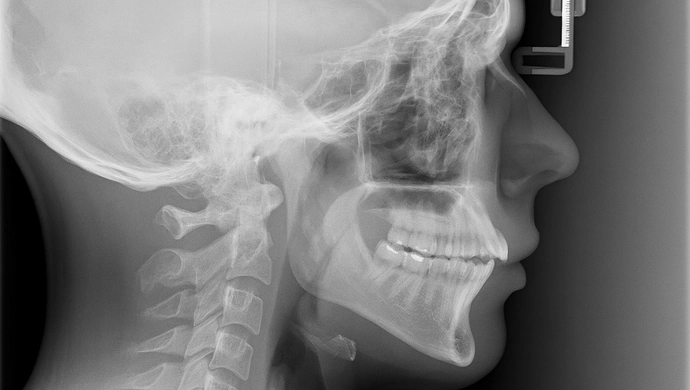

Fałszywe narodziny i zdjęcia RTG z internetu. Mieszkaniec gminy Wschowa usłyszał 84 zarzuty